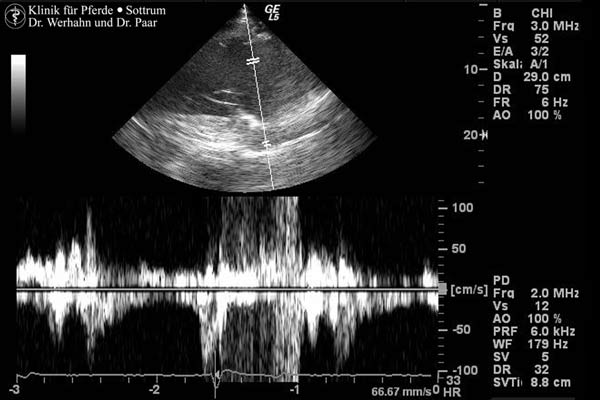

Herzklappenfehler und mögliche daraus resultierende Dimensionsveränderungen am Herzen (z.B. Vorhofdilatationen) werden durch eine Ultraschalluntersuchung abgeklärt.

Hierfür steht uns ein Ultraschallgerät zur Verfügung, das bei hoher Auflösung eine besonders hohe Eindringtiefe hat und neben der herkömmlichen Untersuchung im b-Mode auch mit m-Mode- und Farbdoppler-Technik ausgestattet ist. Durch die Doppler-Technik werden Blutströme und ihre Turbulenzen dargestellt.

Herznebengeräusche, die beim Abhören des Pferdes auffallen, beruhen in den meisten Fällen auf einen unvollständigen Schluss einzelner Herzklappen ("Herzklappenfehler"). Durch die Ultraschalluntersuchung kann abgeklärt werden, ob dies für die Leistungsfähigkeit von Bedeutung ist und ob es eine Auswirkung auf den aktuellen Gesundheitszustand hat.

Die Herzultraschalluntersuchung wird nicht selten auch im Zusammenhang mit Kaufuntersuchungen durchgeführt und hat natürlich auch Bedeutung für die Einschätzung des Narkoserisikos. Sie ist desweiteren unverzichtbar bei dem Entscheid über die Behandlung von Pferden mit Vorhofflimmern. Bei starken Dimensionsveränderungen am Herzen ist die Prognose für eine dauerhaft erfolgreiche medikamentöse Entflimmerung schlecht.